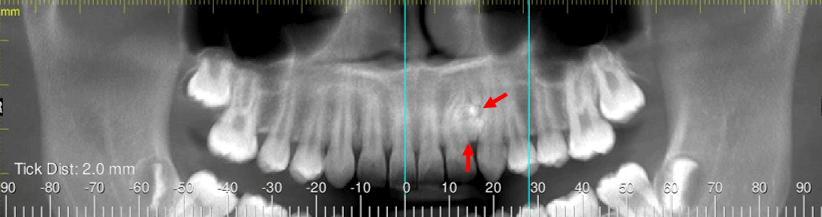

Fig.1

En la evaluación de la tomografía para dientes impactados, se realizó la reconstrucción panorámica del maxilar superior (Fig.1), en la cual se observa una imagen de densidad mixta y heterogénea, localizada entre los órganos dentarios 22 y 23. Nótese las diferentes densidades del objeto señalado con flechas rojas y la dilaceración radicular del órgano dentario 22.